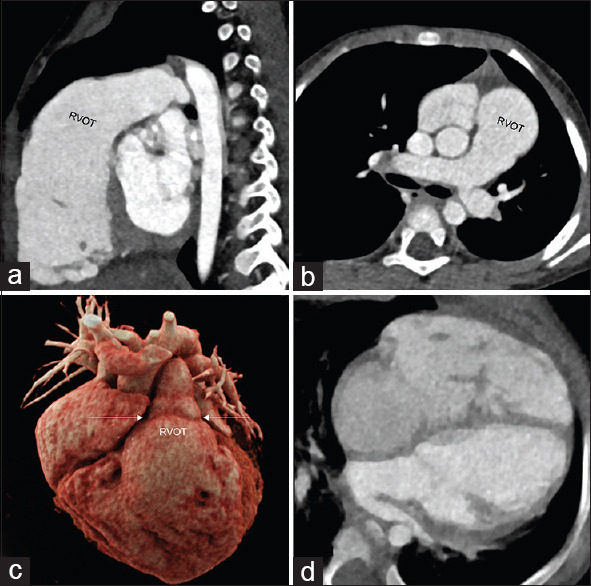

Absent pulmonary valve syndrome, commonly linked with tetralogy of Fallot and ventricular septal defect, is a rare congenital condition. It is exceedingly rare to have an isolated absent pulmonary valve with an intact ventricular septum without cardiovascular shunt lesions, such as an atrial/ventricular septal defect or patent ductus arteriosus. This report presents a case of such rarity involving a young child with recurrent lower respiratory tract infections.